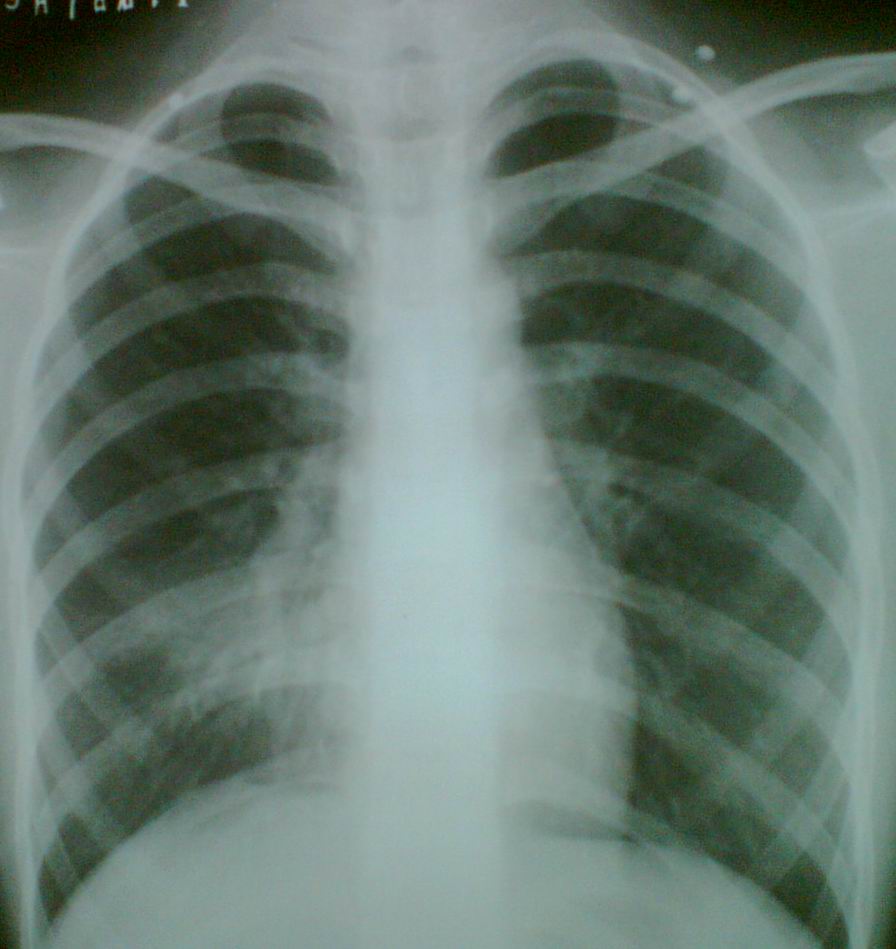

女,12岁,咳嗽,抗炎12天未痊愈行胸片检查(中途有好转后又复发),大家看看有没有右肺中叶综合征的可能?

右下肺门区片絮状阴影,右心缘模糊,首先考虑炎症。

右肺中叶实变,建议加照右侧位片。或ct检查。

考虑右肺中叶肺炎;建议抗炎治疗后复查。